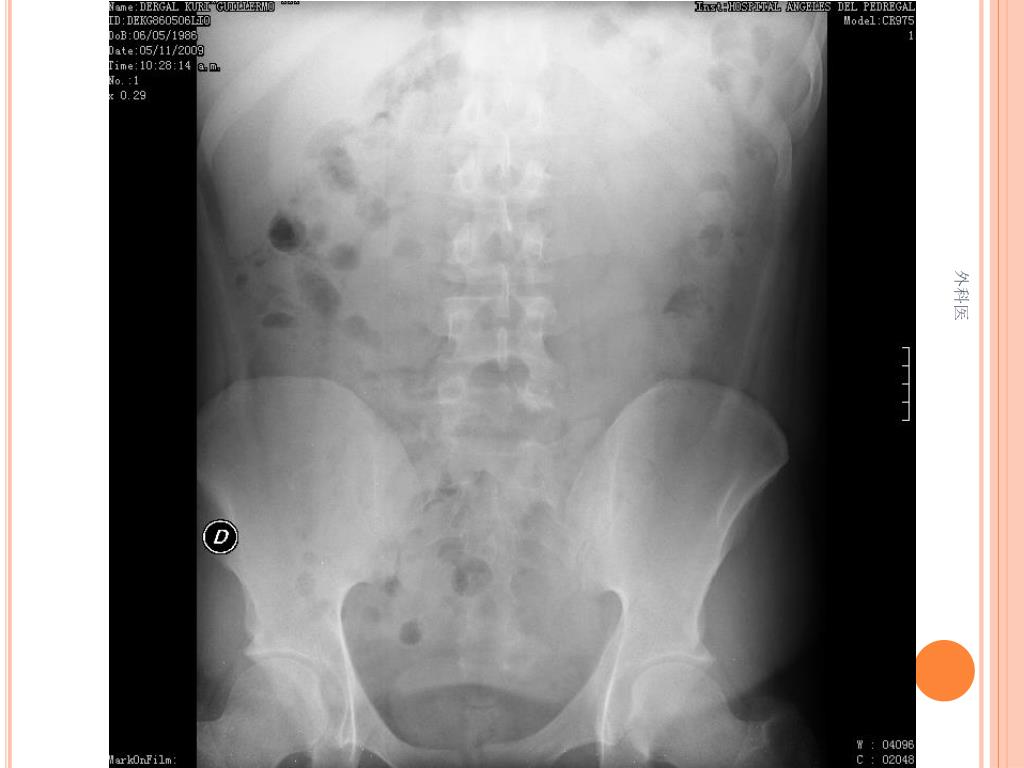

44. Tips • Leucocitos Mas de 20000/ml • Mas de 20% de la apéndices no se llenan con el bario por enema. • USG sensibilidad del 85% y Especificidad de mas 90% para Apendicitis Aguda. • TAC de Abdomen cortes de 5mm, sensibilidad y especificidad del 90% para dolor abdominal. • Analisis de 75000, taza de apendice negativa de 6% Hombres y 13% Mujeres 外科医